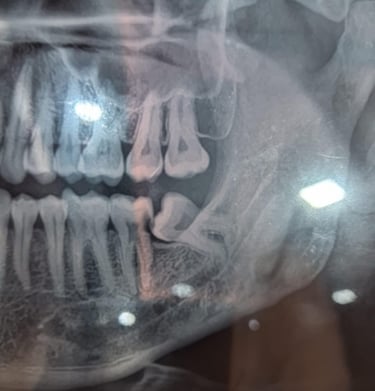

Impacted Tooth Surgery

Impacted teeth may be monitored if symptom-free. Surgery is common for wisdom teeth, while orthodontic aids can help guide tooth eruption.